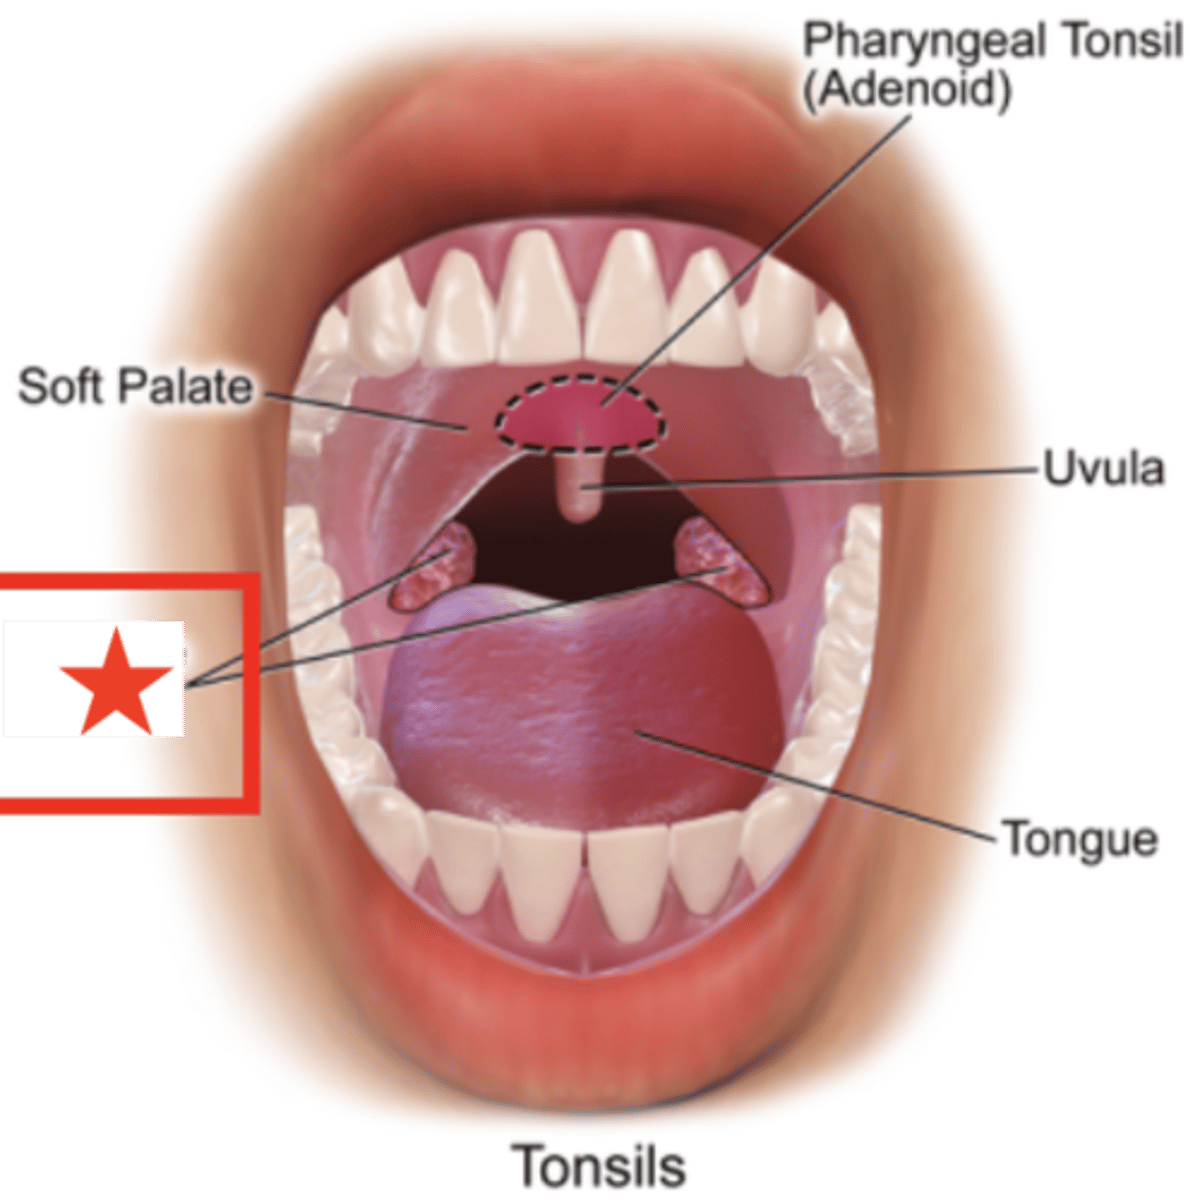

name the circled region

oropharynx

name the circled region

palatine tonsils

pharyngeal tonsils

lingual tonsils

laryngopharynx

name the circled region

palatine tonsils (surface anatomy)